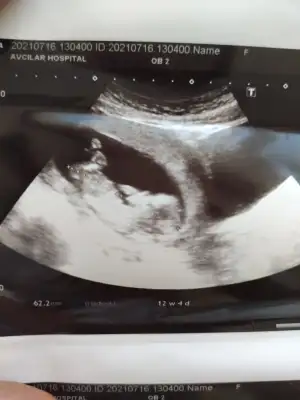

Yas riski tek basina birsey anlam ifade etmiyormus

Allah bağışlasın, evladınız sağ selamet kolaylıkla kucagınıza alın inşallah gözünüz aydın![]()